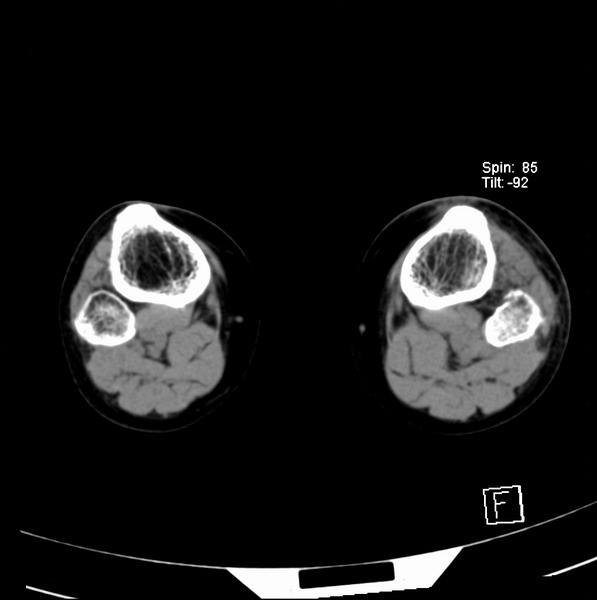

标题: CT21917:右腓骨小头是否骨软骨瘤? [打印本页]

标题: CT21917:右腓骨小头是否骨软骨瘤?

女、43.

不是骨软骨瘤,“牵拽征”,正常变异。有平片吗?

正常变异,“牵拽征”,比目鱼肌牵拽.

比目鱼肌附着点